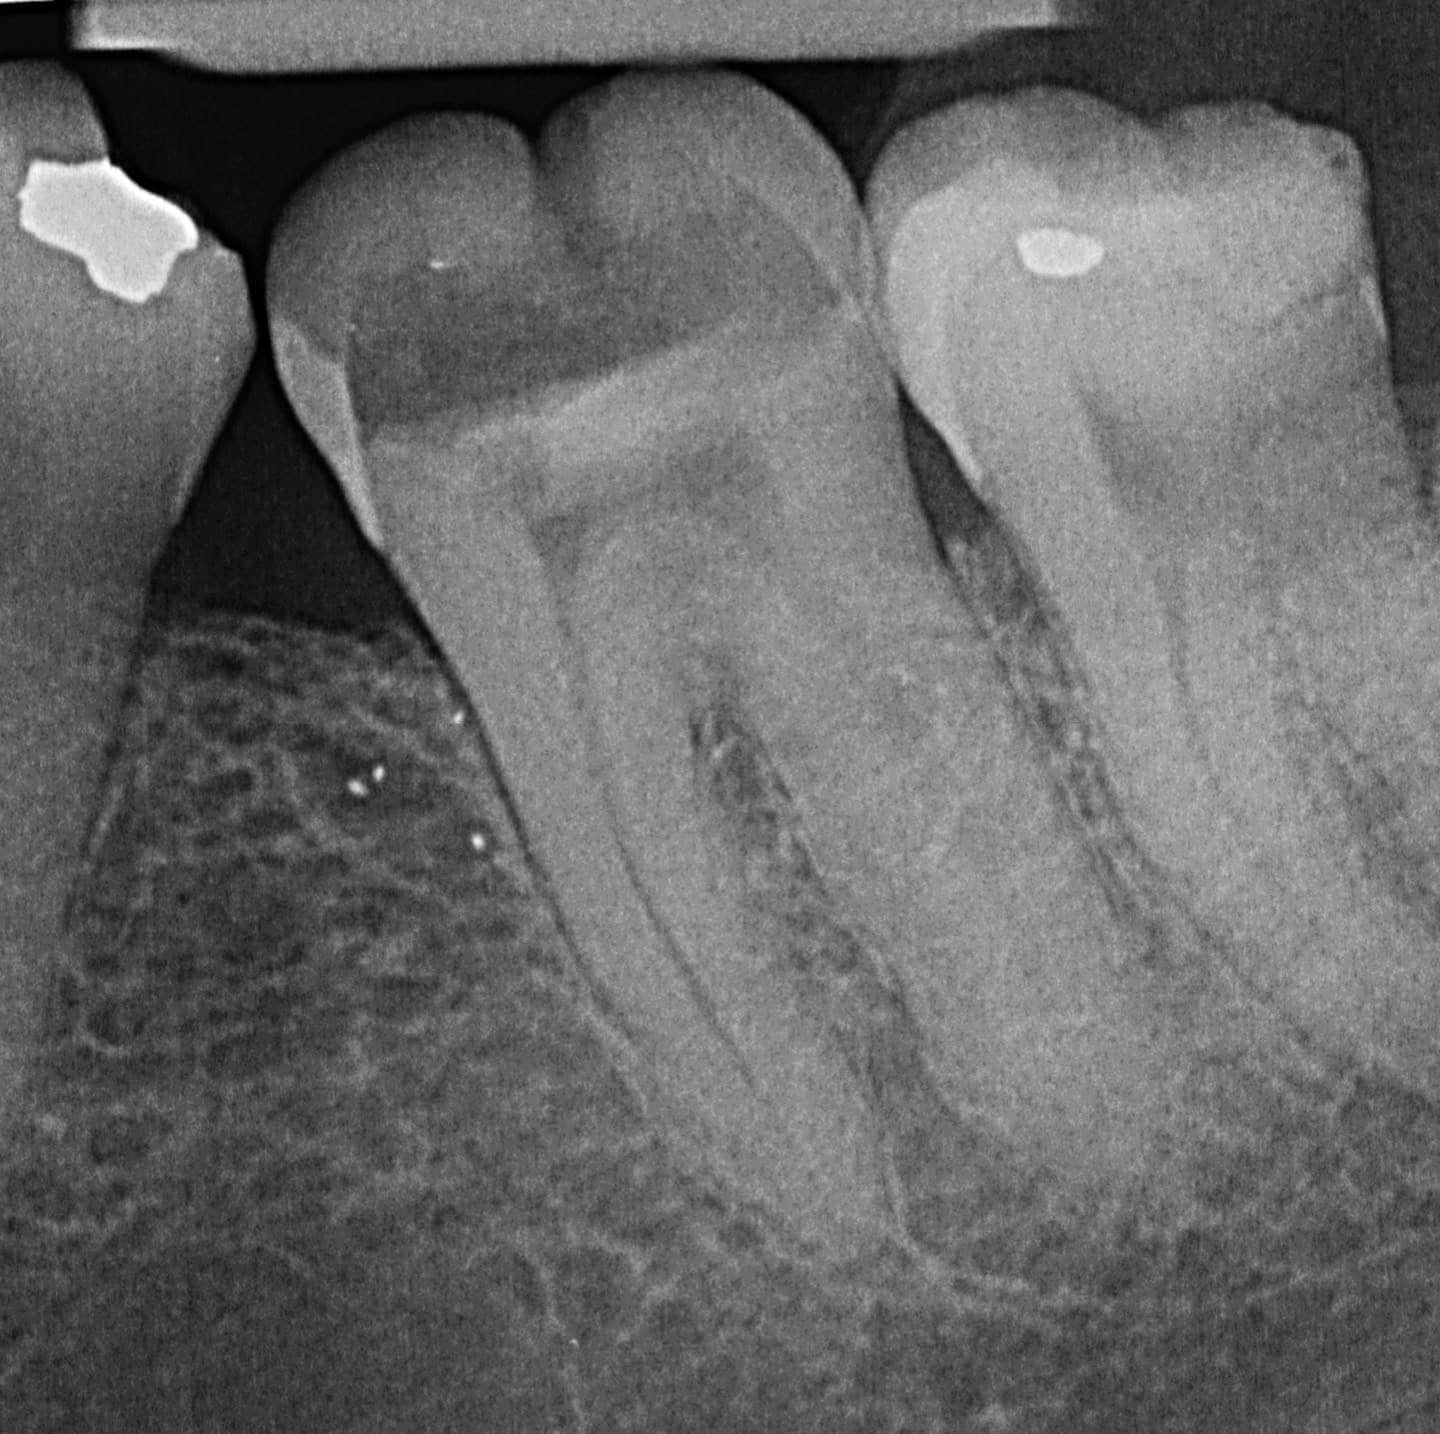

Karies frühzeitig entdecken, damit sie den Nerven nicht beschädigt

Moderne Diagnose- und Behandlungsverfahren: Einsatz digitaler Röntgentechnologie und elektrischer Längenmessung für genaue Diagnosen und erfolgreiche Behandlungschancen.

Regelmässige Röntgendiagnostik kann dabei helfen, einer Wurzelkanalbehandlung vorzubeugen. Hierbei wird die Suffizienz vorhandener Restaurationen sowie die Kariesprogredienz beurteilt.